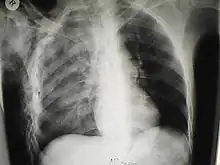

Significant cases of subcutaneous emphysema are easy to diagnose because of the characteristic signs of the condition.[1] In some cases, the signs are subtle, making diagnosis more difficult.[13] Medical imaging is used to diagnose the condition or confirm a diagnosis made using clinical signs. On a chest radiograph, subcutaneous emphysema may be seen as radiolucent striations in the pattern expected from the pectoralis major muscle group. Air in the subcutaneous tissues may interfere with radiography of the chest, potentially obscuring serious conditions such as pneumothorax.[18] It can also reduce the effectiveness of chest ultrasound.[27] On the other hand, since subcutaneous emphysema may become apparent in chest X-rays before a pneumothorax does, its presence may be used to infer that of the latter injury.[13] Subcutaneous emphysema can also be seen in CT scans, with the air pockets appearing as dark areas. CT scanning is so sensitive that it commonly makes it possible to find the exact spot from which air is entering the soft tissues.[13] In 1944, M.T. Macklin and C.C. Macklin published further insights into the pathophysiology of spontaneous Macklin's Syndrome occurring as a result of a severe asthmatic attack.

A chest X-ray of a right sided pulmonary contusion associated with flail chest and subcutaneous emphysema